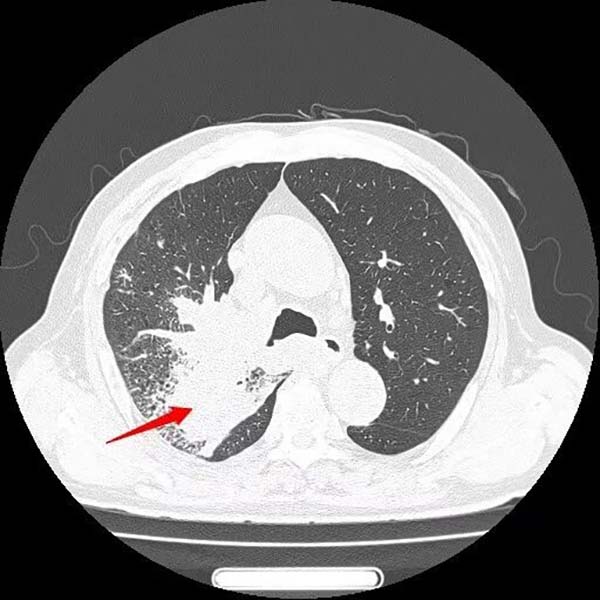

患者王大爷一年前体检发现右肺上叶有一约6×4mm结节,当时未予重视。一年后,他突然出现活动后喘憋症状,复查胸部CT显示右肺上叶后段出现约50×50mm不规则实性团块,影像学高度怀疑肺恶性肿瘤。

经过一个周期的治疗后,患者喘憋、咳嗽等呼吸道症状明显缓解,复查影像显示右肺上叶肿物显著缩小,疗效评估良好。这一结果让患者及家属重拾治疗信心,也为下一阶段治疗奠定了基础。